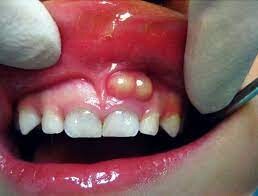

What Is A Tooth Abscess?

A tooth abscess is a bacterial infection found in the inner part of the tooth where pus has collected and can cause moderate to severe pain in people who suffer from the condition. Tooth abscesses can occur when a cavity has gone untreated for too long or when a crack or chip in the tooth allows bacteria to find its way into the dental pulp (the inner, soft part of the tooth) area of the tooth and gets infected.

Once the bacteria has made its way inside, it will spread down to the root and cause both inflammation and swelling. Once inflammation occurs, it will force the pus into a tight space (known as the abscess) at the tip of the root where the swelling exists.

Symptoms

Signs and symptoms of a tooth abscess include:

Persistent, throbbing or severe toothache

Extreme temperature sensitivity

Pain when performing normal chewing or biting

Fever

Swelling in the face or the cheeks

Lymph nodes under the jaw or in the neck become tender or swollen

A rush of foul-tasting fluid in the mouth followed by cessation of pain, which means the abscess has ruptured

If you experience any of the signs or symptoms listed above, you should see your dentist immediately, especially if you begin to experience swelling in your face or begin to feel feverish. If your dentist cannot see you immediately, you should go to an emergency room as it’s possible these symptoms indicate the infection is possibly spreading into your jaw and the surrounding tissue.

The only way to rid yourself of both the pain and the condition is to get proper dental treatment. You may feel a lessening of pain if the abscess ruptures, but you’ll still need to get a professional’s help. The infection could spread to other parts of your jaw and beyond to parts of your head and neck and, in a worst-case scenario, lead to sepsis, which is an infection throughout the entire body that can put your life at risk.